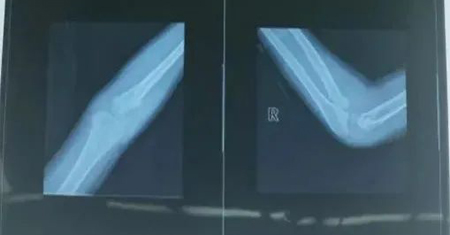

小儿骨科吕学敏主任医师、李强医生火速接诊,诊断为右桡骨颈骨折,右尺骨鹰嘴骨折。由于患儿骨折移位大,复位困难,经小儿骨科专家组会诊后建议急诊手术。患儿家长心情紧张焦躁,医生安慰他说:“请放心,孩子一定会平安。”

患儿15:40入室,在臂丛联合静脉全麻下行右侧桡骨颈闭合复位弹性髓内针内固定。在手术医生、麻醉医生和护士们的通力合作下,患儿平稳安全地完成了手术。当等候在手术室外的家长看到孩子被平安推出后,不禁热泪盈眶,连连感谢。